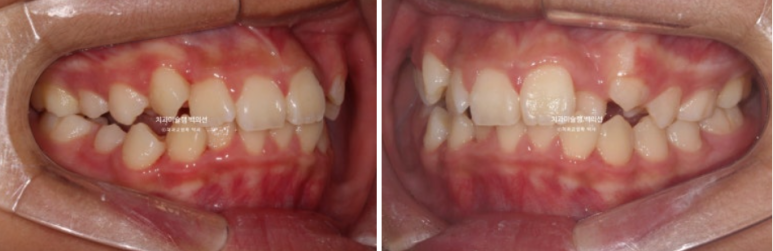

24.02

악궁확장을 통한 덧니배열을 목표로 인비절라인퍼스트 교정치료 권유드렸습니다.